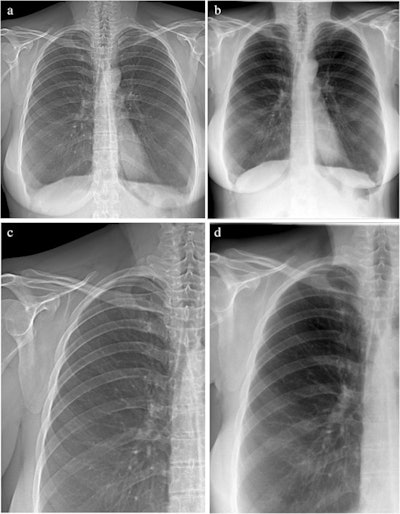

A team led by Margarete Kattau of the Technical University of Munich in Germany compared the visual quality of attenuation images obtained with the prototype with those from a commercial radiography system. Overall image quality was rated by readers as high for both devices, a finding that advances the prototype toward clinical use, the researchers suggest.

Overall image quality was rated high for both devices, 4.2 for the prototype and 4.6 for the commercial system, according to the results. The rating scores varied only slightly between both image types, especially for structures relevant to lung assessment, where the images from the commercial system were graded slightly higher, the authors wrote.

In addition, for the assessment of motion artifacts, the images from the commercial system achieved a mean rating of 4.9, whereas the grating-based images from the prototype scored 4.1 on average.